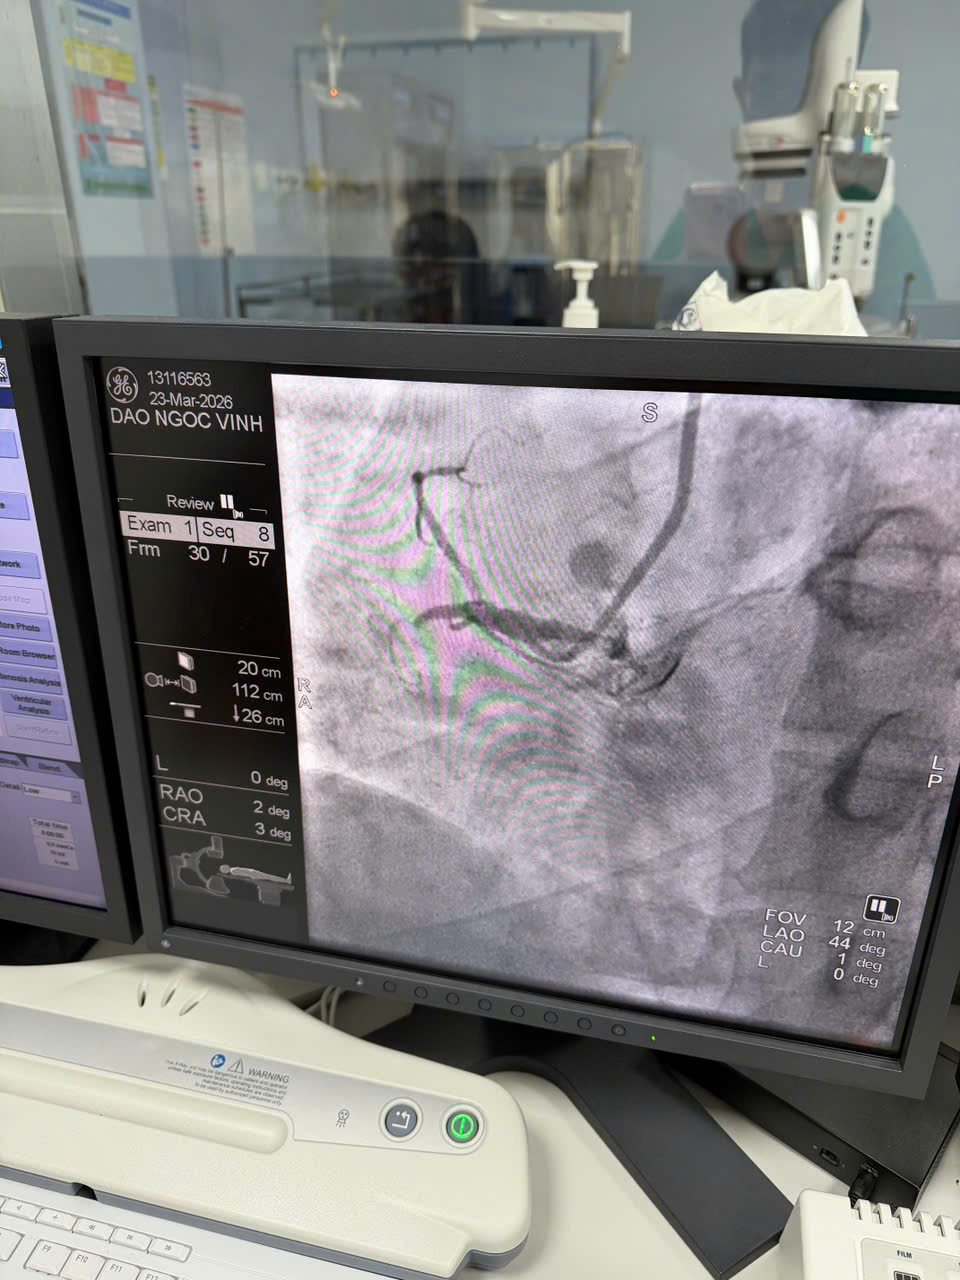

Hình ảnh vị trí mạch máu bị tắc nghẽn của bệnh nhân Đ.N.V

Nhờ sự phối hợp nhịp nhàng và chính xác, chỉ sau 27 phút tập trung cao độ, toàn bộ mạch vành bị tắc nghẽn đã được tái thông hoàn toàn. Kết quả thành công ngoài mong đợi khi ngay trên bàn can thiệp, bệnh nhân dứt hẳn cơn đau ngực, các chỉ số sinh hiệu trở về mức ổn định, giúp ông vượt qua tình trạng nguy kịch..